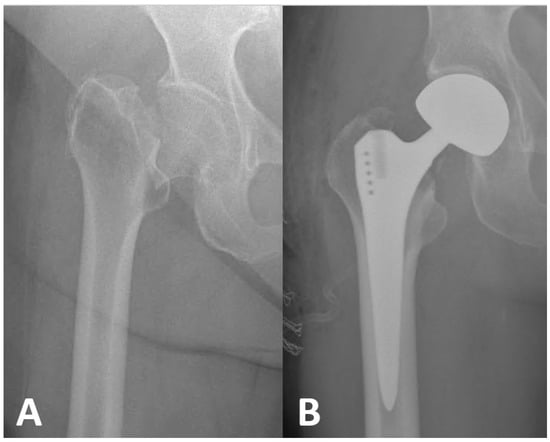

2.3. Surgical Technique and Follow-Up Protocol